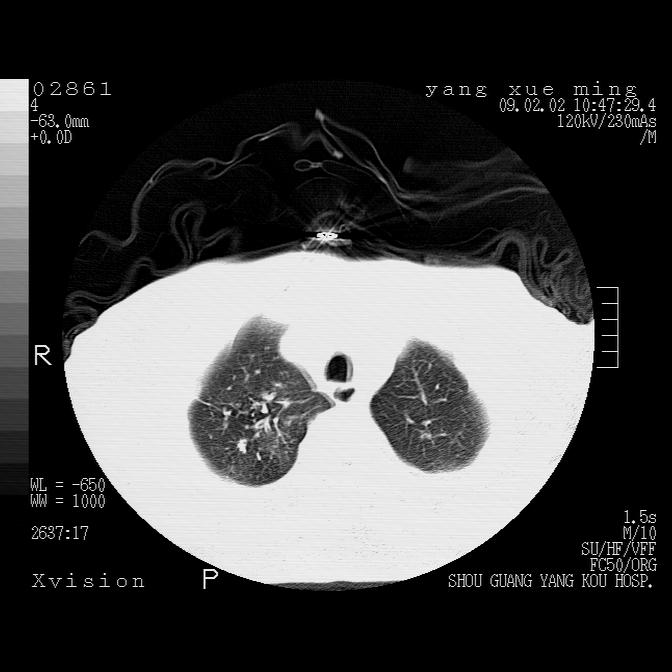

以下是引用lkc8963在2009-2-3 20:11:00的发言:[br]1)右上肺陈旧病灶。2)右下肺团块及团片影,影像表现符合感染。3)左心增大,左冠脉钙化,符合冠心病。4)双侧肺门扩大,以左侧为著,肺动脉干略粗,左上肺局限性气肿,为谨慎起见,需除肿瘤,建议增强。

以下是引用zbp537在2009-2-3 19:08:00的发言:[br]我诊断为肺泡性肺水肿。[br]诊断依据:[br]1、心影普遍增大,肺血管增粗,并见絮状高密度影,肺门改变显著。[br]2、临床上表现胸闷咳嗽,无发烧,不是一个典型的肺部感染的病史。